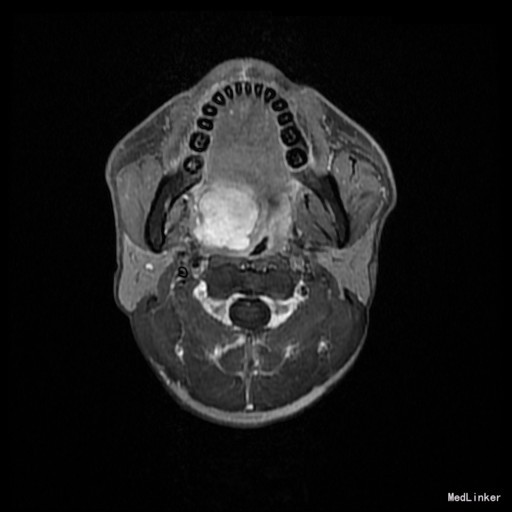

患者:男,42岁 主诉:发现右侧软腭肿物7年余。 病史:患者诉7年余前发现右侧软腭肿物,渐进性增大,无咽痛邓特殊不适。

查体:右侧软腭至硬腭处见一肿物,约5*3cm,质硬,固定,边界欠清,表面粘膜光滑。 辅助检查:外院颌面CT提示:右侧软腭实性占位,并累及鼻咽、口咽壁,建议MRI增强检查。

入院诊断:咽旁肿物(右侧软腭肿物性质待查) 治疗:入院后咽部MRI示:软腭右部软组织肿块,性质待定,鼻咽腔及口咽腔明显变窄。,未见手术禁忌,遂于全麻下行“右侧咽旁间隙肿物切除术”,术程顺利,术后未见并发症。病理:多形性腺瘤。